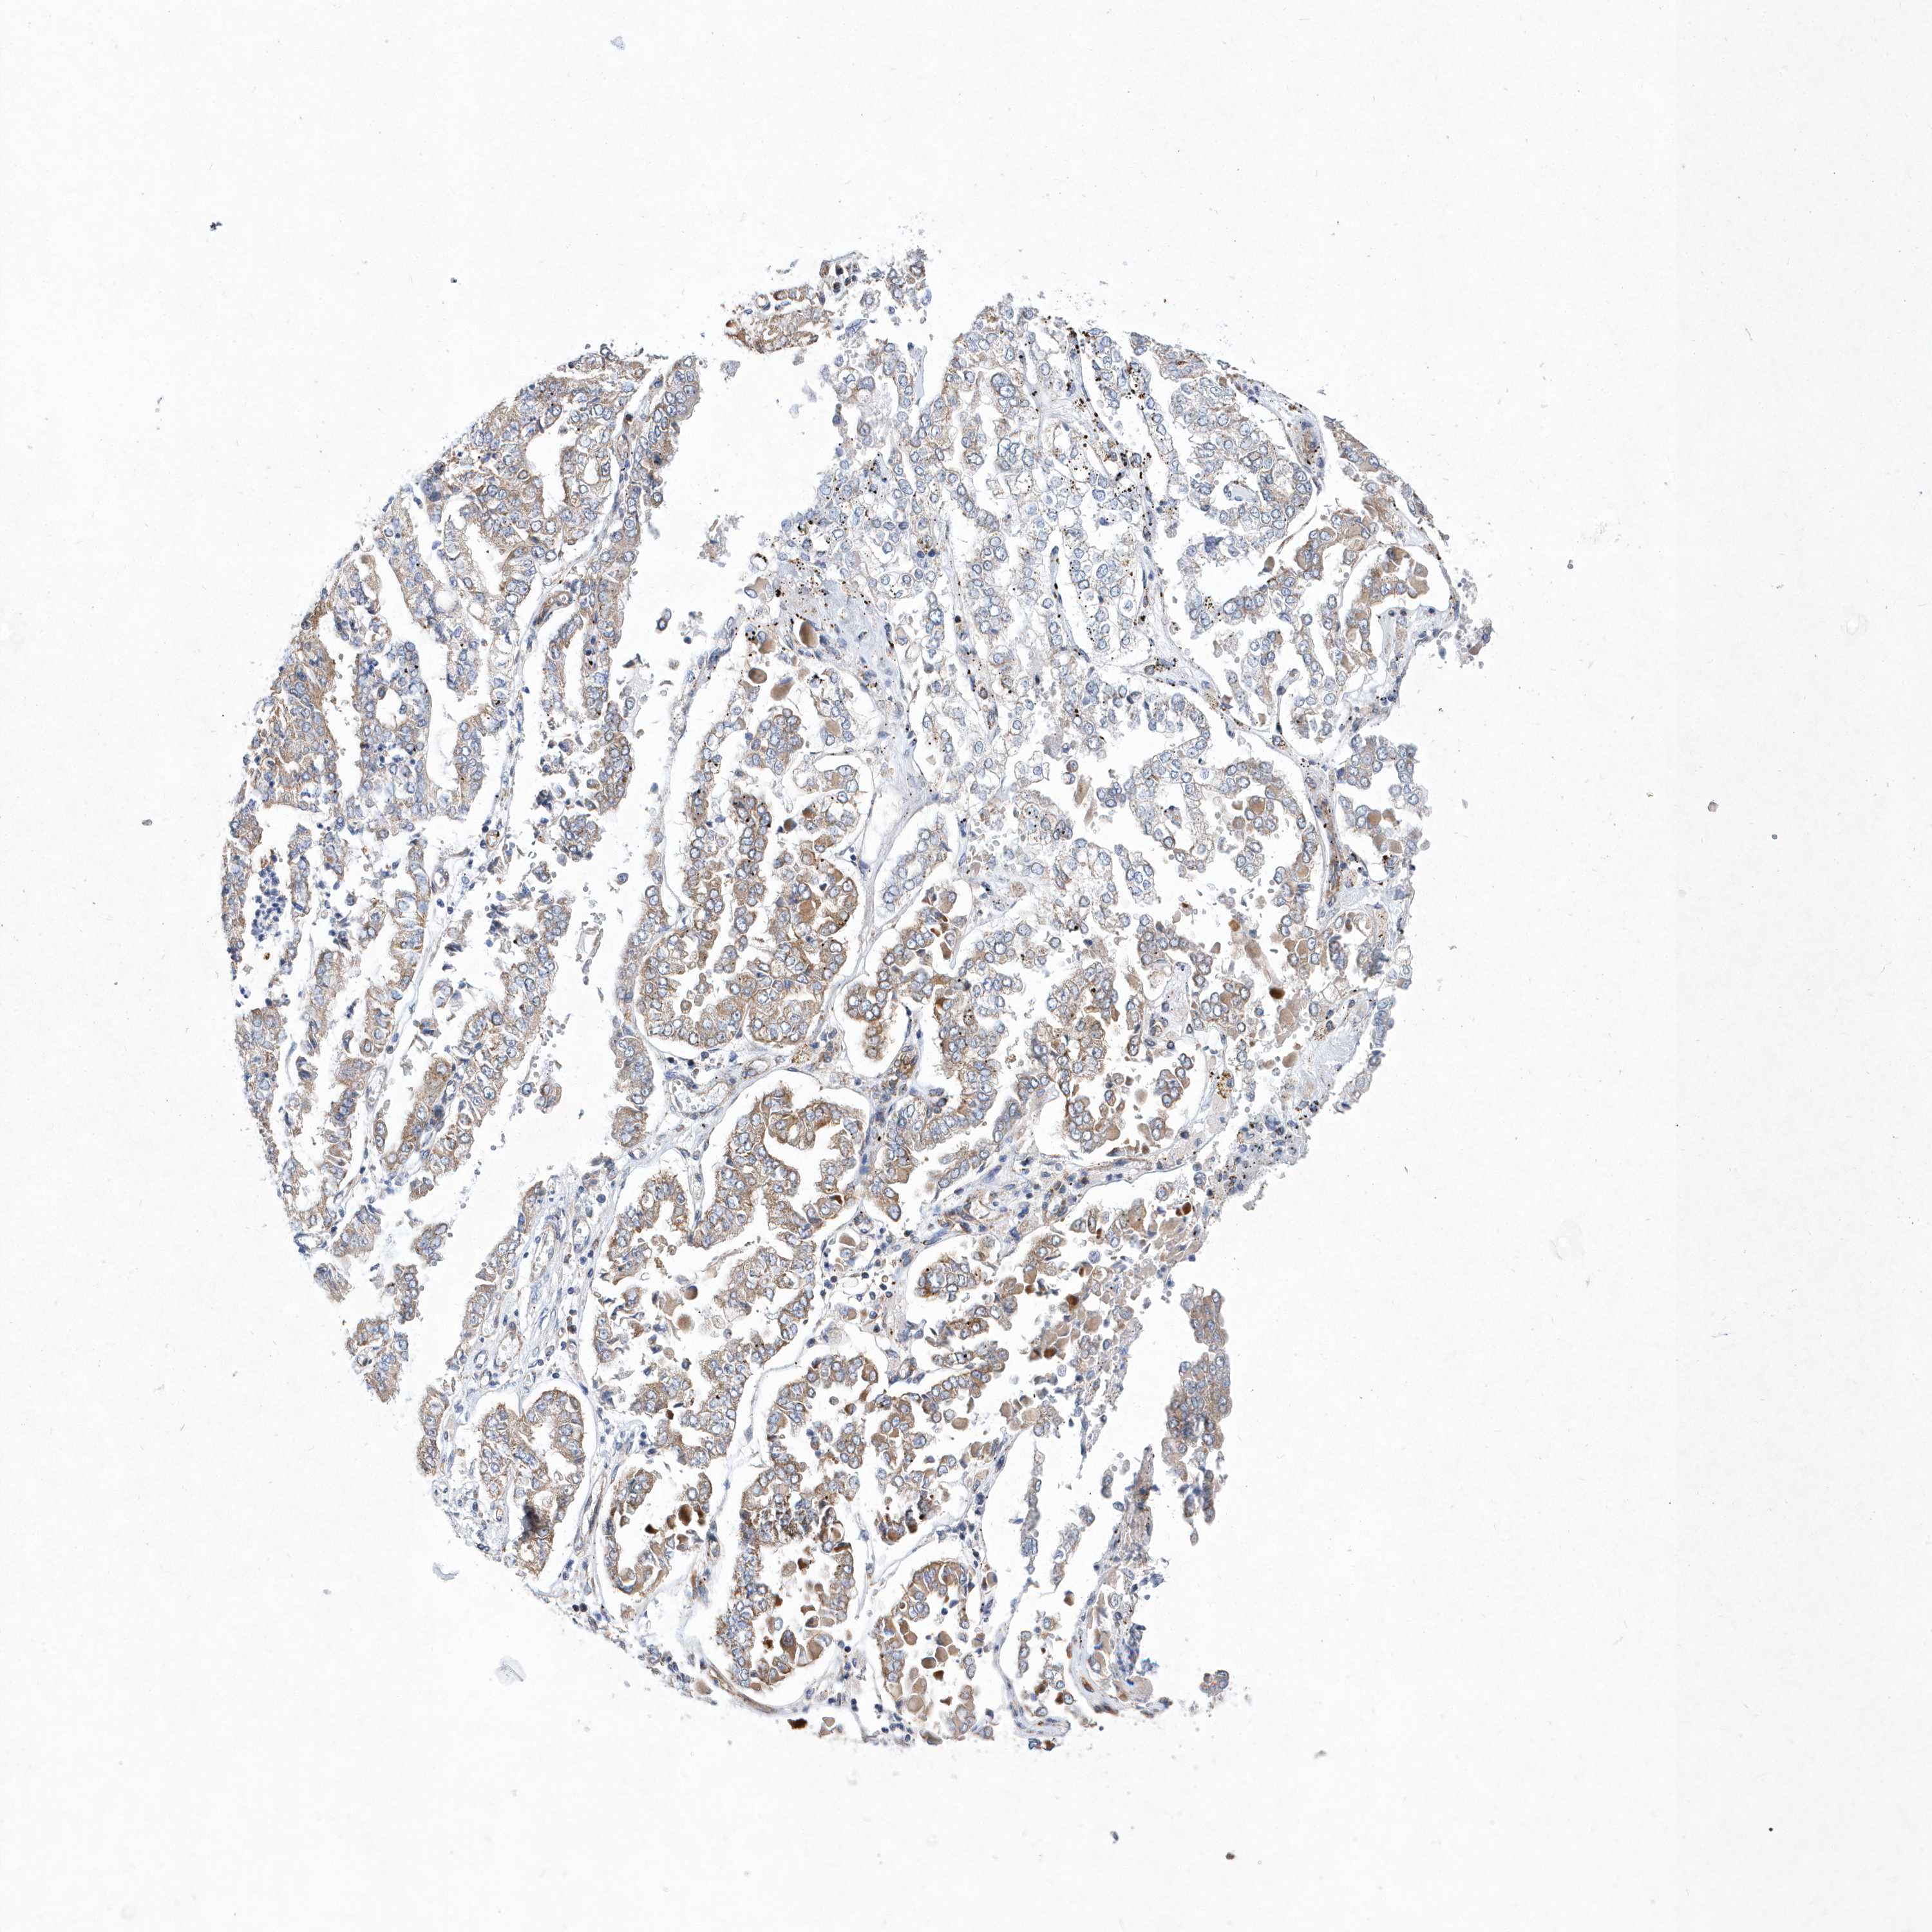

STOMACH CANCER - Protein expressioni

A mouse-over function shows sample information and annotation data. Click on an image to view it in a full screen mode. Samples can be filtered based on level of antibody staining by selecting one or several of the following categories: high, medium, low and not detected. The assay and annotation is described here.

Note that samples used for immunohistochemistry by the Human Protein Atlas do not correspond to samples in the TCGA dataset.

Antibody stainingi

Antibody staining in the annotated cell types in the current human tissue is reported as not detected, low, medium, or high, based on conventional immunohistochemistry profiling in selected tissues. This score is based on the combination of the staining intensity and fraction of stained cells.

Each image is clickable and will lead to virtual microscopy that enables deeper exploration of all samples and also displays staining intensity scores, fraction scores and subcellular localization as well as patient and tissue information for each sample.

Antibody HPA031172

Staining

High

Medium

Low

Not detected

Intensity

Strong

Moderate

Weak

Negative

Quantity

>75%

75%-25%

<25%

None

Location

Nuclear

Cytoplasmic/membranous

Cytoplasmic/membranous,nuclear

Adenocarcinoma, NOS